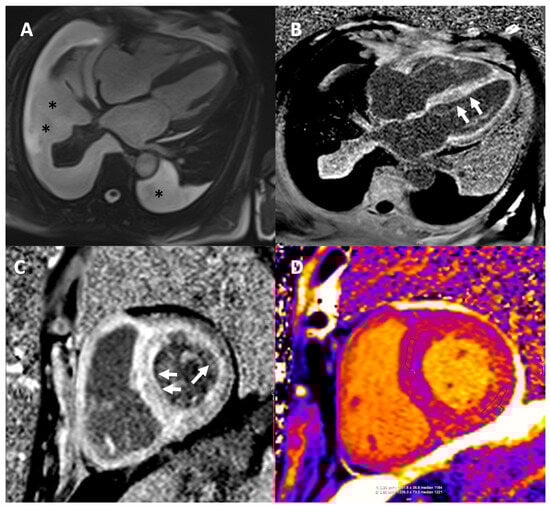

7. Cardiac Magnetic Resonance

7.1. CMR for Diagnosis

- Burrage, M.K.; Ferreira, V.M. Cardiovascular Magnetic Resonance for the Differentiation of Left Ventricular Hypertrophy. Curr. Heart Fail. Rep. 2020, 17, 192–204. [Google Scholar] [CrossRef]

- Licordari, R.; Trimarchi, G.; Teresi, L.; Restelli, D.; Lofrumento, F.; Perna, A.; Campisi, M.; de Gregorio, C.; Grimaldi, P.; Calabrò, D.; et al. Cardiac Magnetic Resonance in HCM Phenocopies: From Diagnosis to Risk Stratification and Therapeutic Management. J. Clin. Med. 2023, 12, 3481. [Google Scholar] [CrossRef]

- Maceira, A.M.; Joshi, J.; Prasad, S.K.; Moon, J.C.; Perugini, E.; Harding, I.; Sheppard, M.N.; Poole-Wilson, P.A.; Hawkins, P.N.; Pennell, D.J. Cardiovascular Magnetic Resonance in Cardiac Amyloidosis. Circulation 2005, 111, 186–193. [Google Scholar] [CrossRef]

- Syed, I.S.; Glockner, J.F.; Feng, D.L.; Araoz, P.A.; Martinez, M.W.; Edwards, W.D.; Gertz, M.A.; Dispenzieri, A.; Oh, J.K.; Bellavia, D.; et al. Role of Cardiac Magnetic Resonance Imaging in the Detection of Cardiac Amyloidosis. JACC Cardiovasc. Imaging 2010, 3, 155–164. [Google Scholar] [CrossRef]

- Karamitsos, T.D.; Piechnik, S.K.; Banypersad, S.M.; Fontana, M.; Ntusi, N.B.; Ferreira, V.M.; Whelan, C.J.; Myerson, S.G.; Robson, M.D.; Hawkins, P.N.; et al. Noncontrast T1 Mapping for the Diagnosis of Cardiac Amyloidosis. JACC Cardiovasc. Imaging 2013, 6, 488–497. [Google Scholar] [CrossRef]

- Baggiano, A.; Boldrini, M.; Martinez-Naharro, A.; Kotecha, T.; Petrie, A.; Rezk, T.; Gritti, M.; Quarta, C.; Knight, D.S.; Wechalekar, A.D.; et al. Noncontrast Magnetic Resonance for the Diagnosis of Cardiac Amyloidosis. JACC Cardiovasc. Imaging 2020, 13, 69–80. [Google Scholar] [CrossRef]

- Brooks, J.; Kramer, C.M.; Salerno, M. Markedly Increased Volume of Distribution of Gadolinium in Cardiac Amyloidosis Demonstrated by T1 Mapping. J. Magn. Reason. Imaging 2013, 38, 1591–1595. [Google Scholar] [CrossRef]

- Martinez-Naharro, A.; Kotecha, T.; Norrington, K.; Boldrini, M.; Rezk, T.; Quarta, C.; Treibel, T.A.; Whelan, C.J.; Knight, D.S.; Kellman, P.; et al. Native T1 and Extracellular Volume in Transthyretin Amyloidosis. JACC Cardiovasc. Imaging 2019, 12, 810–819. [Google Scholar] [CrossRef]

- Pan, J.A.; Kerwin, M.J.; Salerno, M. Native T1 Mapping, Extracellular Volume Mapping, and Late Gadolinium Enhancement in Cardiac Amyloidosis: A Meta-Analysis. JACC Cardiovasc. Imaging 2020, 13, 1299–1310. [Google Scholar] [CrossRef]